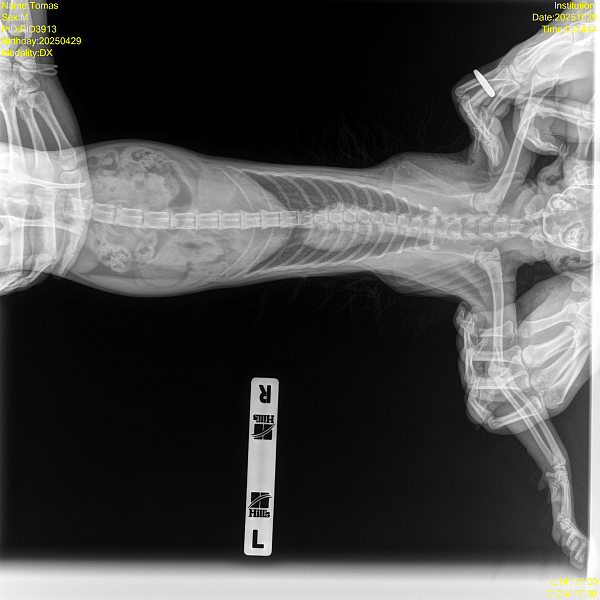

Рентген - смотрел кардиолог, сказал ничего патологического не видит, но может лучше показать пульмонологу для второго мнения.

Прикладываю заключение узи, рентген и видео.

Здравствуйте, дыхание с открытым ртом у кошек при активной физической активности и сильном беспокойстве это может быть вариантом нормы, а вот кашель нет. Наиболее частые причины кашля у кошек это бронхит и астма, дифференцировать эти состояния по рентгену невозможно. Если приступы кашля становятся частыми, то для уточнения диагноза назначают дополнительную диагностику - КТ грудной полости, бронхоальвеолярный лаваж. Если нет возможности провести такую диагностику, то начинаются эмпирическую терапию, чаще всего с ингаляций.

на Ваших снимках выраженных изменений в грудной полости нет, но нельзя исключать, что при сохранении симптомов особенно в виде кашля изменения появятся со временем, если речь идет о формирующейся хронической проблеме. Поэтому если кашель сохраняется, то снимок нужно повторять через 2-6 месяцев.